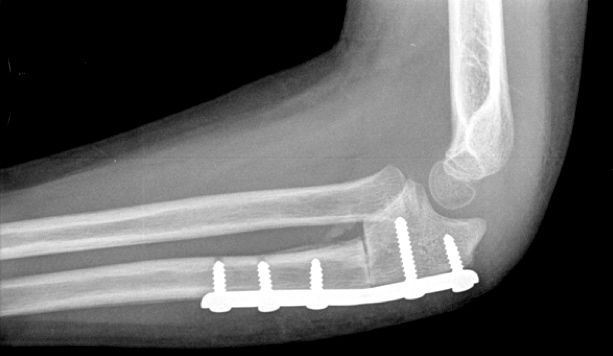

Figura 11: a, b-Fractura metafiso-diafisaria distal inestable. c, d-Control radiológico tras reducción donde se aprecia mala reducción. e, f-Síntesis mediante placa y tornillos.